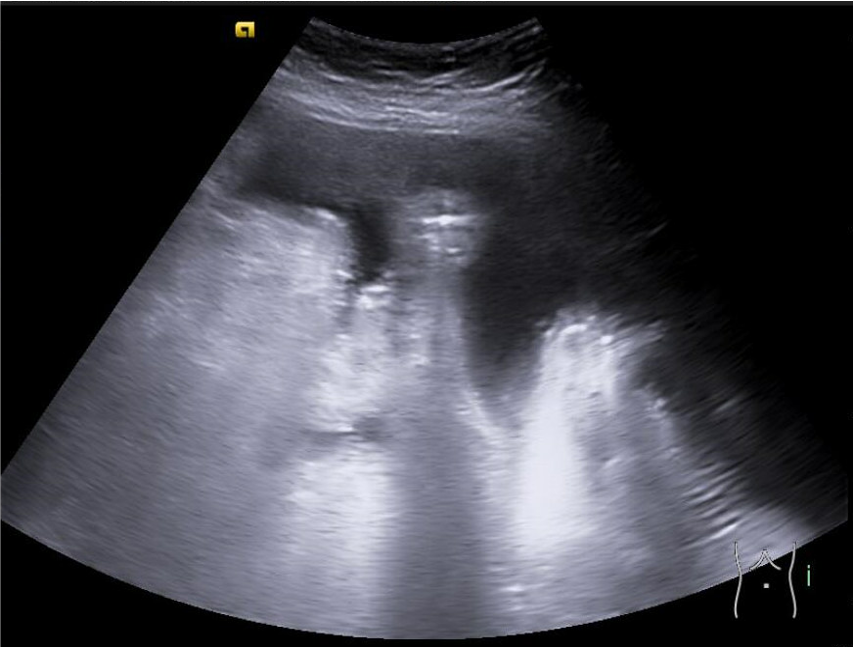

Se realiza ecoPOCUS y se objetiva imágenes anecogénicas en todas las zonas declives, en ambos flancos e hipogastrio y derrame pleural izquierdo.